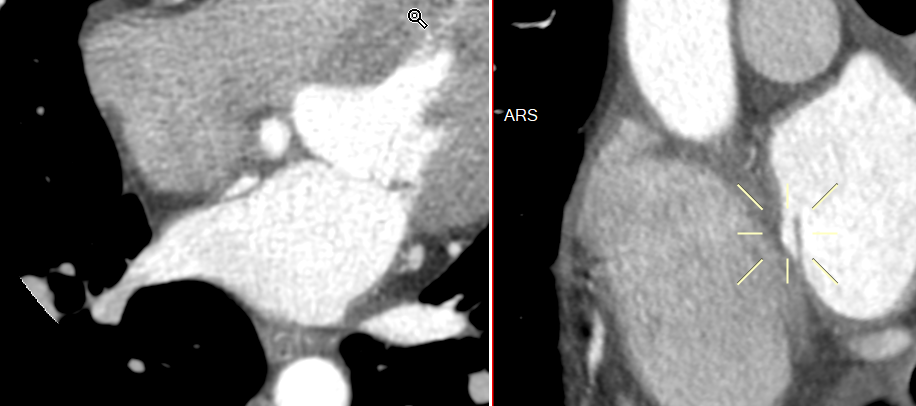

Variante “channel-like”

- Fusion incomplète du septum

- Fréquent

- Asymptomatique ++

- Certains cas sont associés à un FOP